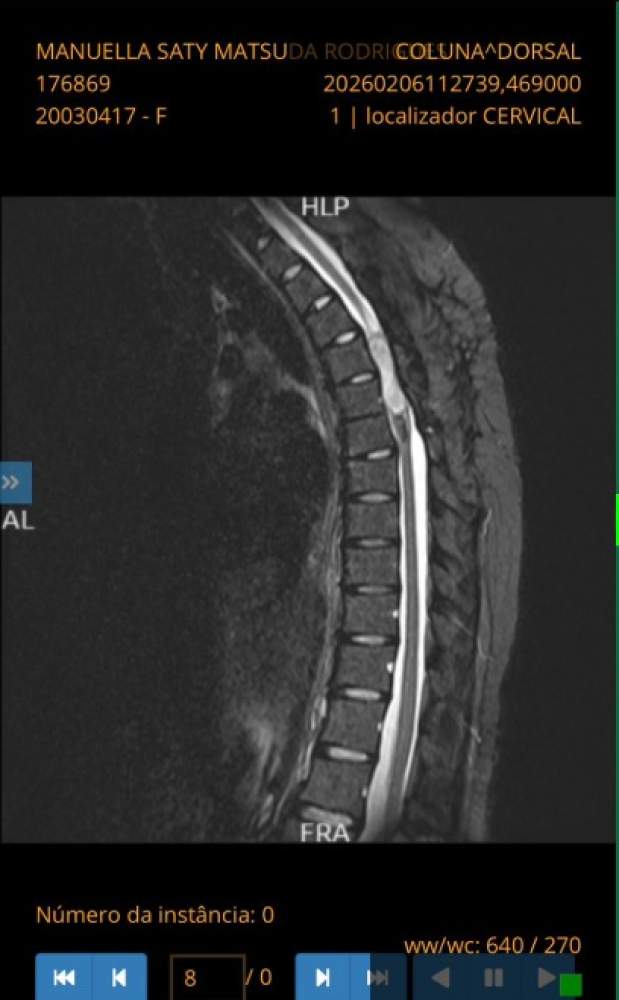

De acordo com familiares, Manuella foi diagnosticada com tumores intramedulares, uma condição rara e de alta complexidade que afeta diretamente a medula espinhal. A doença provoca dores intensas e comprometimento dos movimentos, principalmente nos membros inferiores.

O primeiro diagnóstico ocorreu em 2020, quando a jovem passou por uma cirurgia para retirada de um tumor na região torácica da coluna. Após o procedimento e meses de fisioterapia, conseguiu recuperar parte dos movimentos. Em 2023, um novo tumor foi identificado, exigindo outra cirurgia, com um pós-operatório mais delicado. Na ocasião, Manuella ficou meses sem movimentos da cintura para baixo e precisou de reabilitação intensiva, incluindo acompanhamento no Hospital Sarah Kubitschek, em Brasília.

Agora, em 2026, exames apontaram o crescimento de um novo tumor, com cerca de 5,4 centímetros, o que torna necessária uma nova intervenção cirúrgica com urgência.